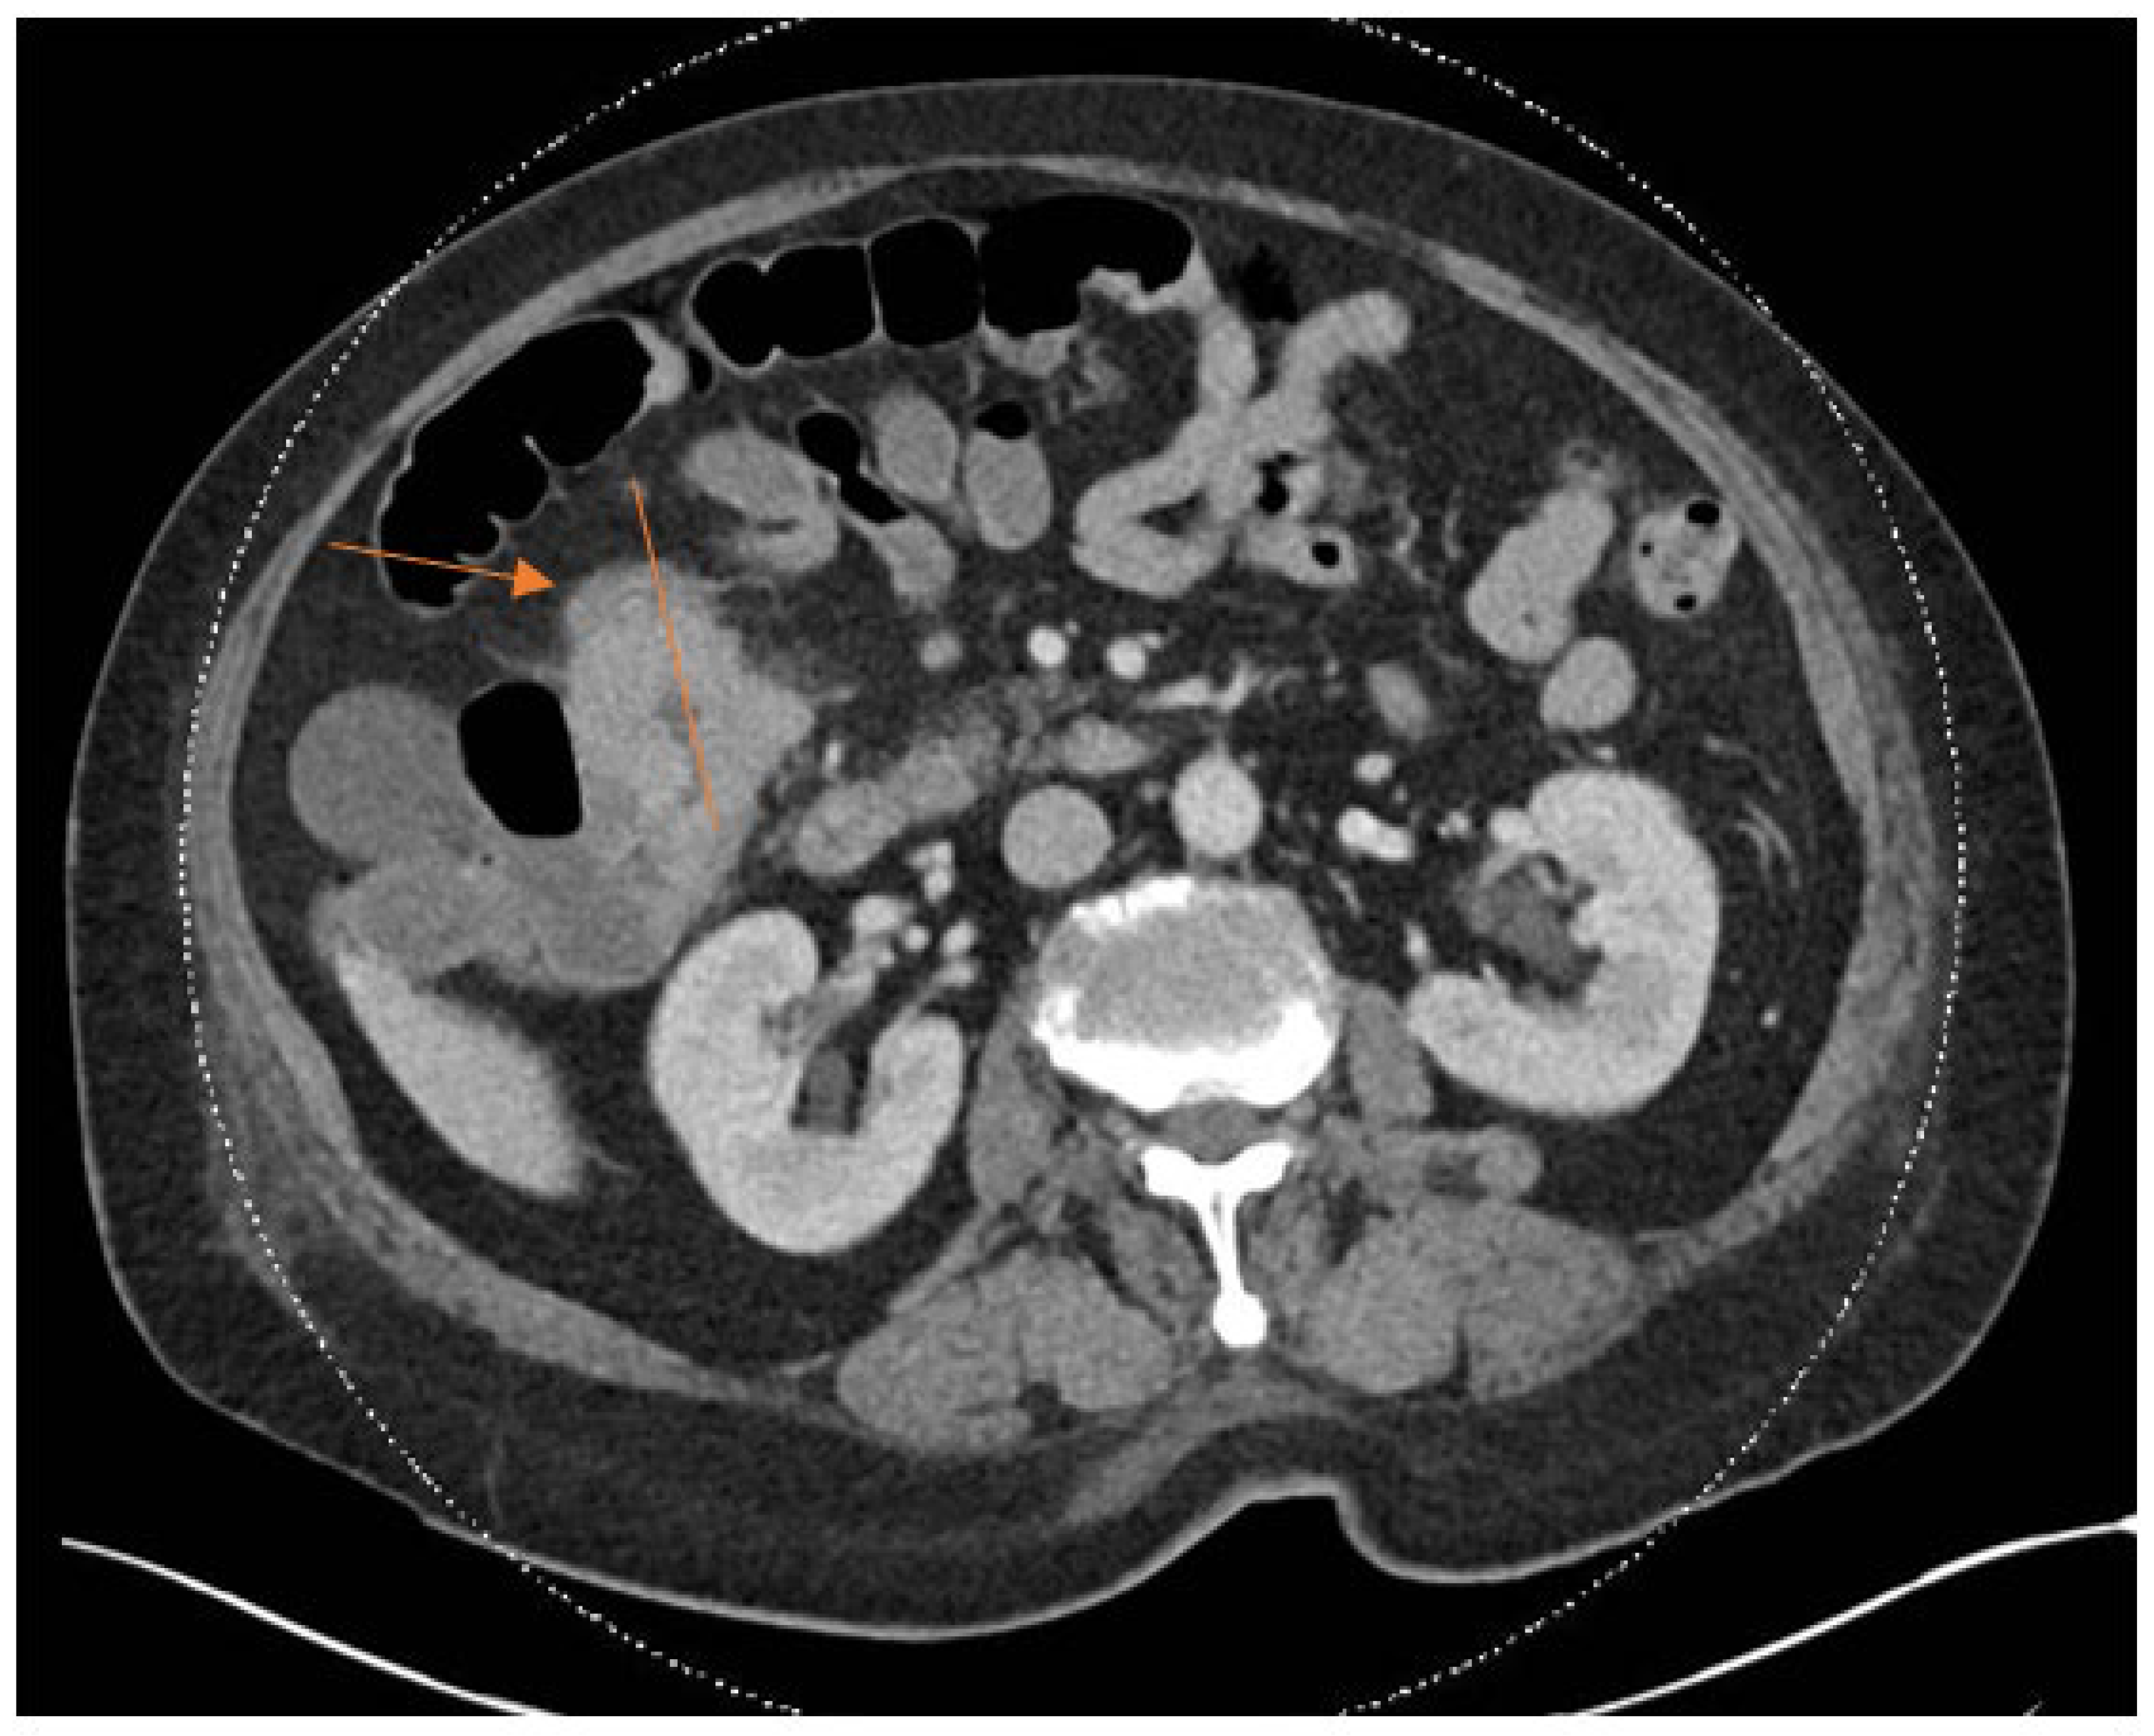

The clinical characteristics of the three cases are summarized in Table 1. The laboratory characteristics of the three cases are summarized in Table 2. All three cases in our study presented with knee pain and swelling at least after five years from the primary total knee arthroplasty. Two out of three cases underwent single-stage revision surgery, whereas one case underwent the DAIR procedure. Laboratory markers indicative of acute inflammatory processes such as CRP and ESR were raised markedly in all three cases. The CT-AP scan performed in Patient 1 showed a colorectal mass, as seen in Figure 1 and Figure 2.

She underwent a single-stage revision surgery. Intraoperative findings revealed copious purulent fluid; and intraoperative cultures confirmed B. fragilis. Postoperative CT-AP revealed a suspicious transverse colon mass. Subsequent colonoscopy confirmed a large proximal transverse colon tumour. Diagnosis of colorectal carcinoma was confirmed with histology showing adenocarcinoma. Computed tomography of the thorax demonstrated incidental pulmonary emboli, and anticoagulation therapy was initiated. She was discharged on long-term intravenous antibiotics and scheduled for definitive colorectal surgery after completing anticoagulation. The patient underwent a total of three months duration of antibiotics, consisting of six weeks of intravenous amoxicillin-clavulanic acid and six weeks of oral metronidazole.

Figure 1. Axial cut of CT-AP scan showing colorectal carcinoma as indicated by arrow.